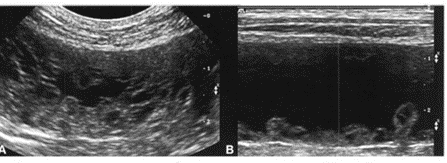

Матка хорошо визуализируется стенки её утолщены, визуализируются множественные округлые, гипоэхогенные и анэхогенные структуры, расположенные в стенке матки-кисты (Рис 2). Эндометрий чаще повышенной хогенности, неравномерно утолщен. Полость органа может быть заполнена гипо/-анэхогенным содержимым.

Рис 2. А-продольное сканирование, конвексный датчик. В-продольное сканирование, линейный датчик. В матке содержится анэхогенная жидкость (синяя стрелка), стенки не равномерно утолщены (красная стрелка), визуализируются множественные анэхогенные кисты (зеленая стрелка)